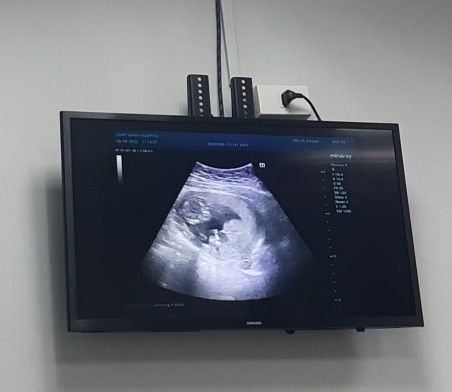

อัตเดตน้องค่ะแม่ๆ วันนี้หมอนัดตรวจอัลตร้าซาวด์ อายุครรภ์ตอนนี้ 10w3d ค่ะ เห็นน้องแล้วค่ะ ตอนตรวจอายุครรภ์ 7w4d ความยาวน้อง 1.31cm ปัจจุบันน้อง 3.57 cm ค่ะ หมอบอกหัวใจน้องเต้นแล้วปกติ น้องกำลังหลับอยู่🥰😁 #ใบอัลตร้าซาวด์แม่ๆบางคนเห็นตัวน้องชัดแจ๋วเลยของเราเป็นเพราะหนังท้องหนาหรือเครื่องตรวจคุณหมอหรือเปล่าคะ😅